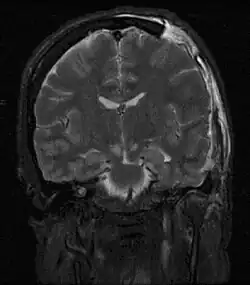

Severely high ICP can cause the brain to herniate.

Severely raised ICP, if caused by a unilateral space-occupying lesion (e.g. a hematoma) can result in midline shift, a dangerous sequela in which the brain moves toward one side as the result of massive swelling in a cerebral hemisphere. Midline shift can compress the ventricles and lead to hydrocephalus.[21]